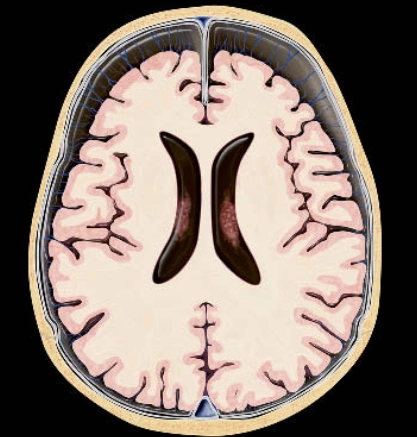

• Não úng thủy tắc nghẽn ở não thất (Obstructive Hydrocephalus)

• Não úng thủy tắc nghẽn ngoài não thất (EVOH - Extraventricular Obstructive Hydrocephalus)

• Hẹp cống não (Aqueductal Stenosis)

• Não úng thủy áp lực bình thường (NPH - Normal-Pressure Hydrocephalus)